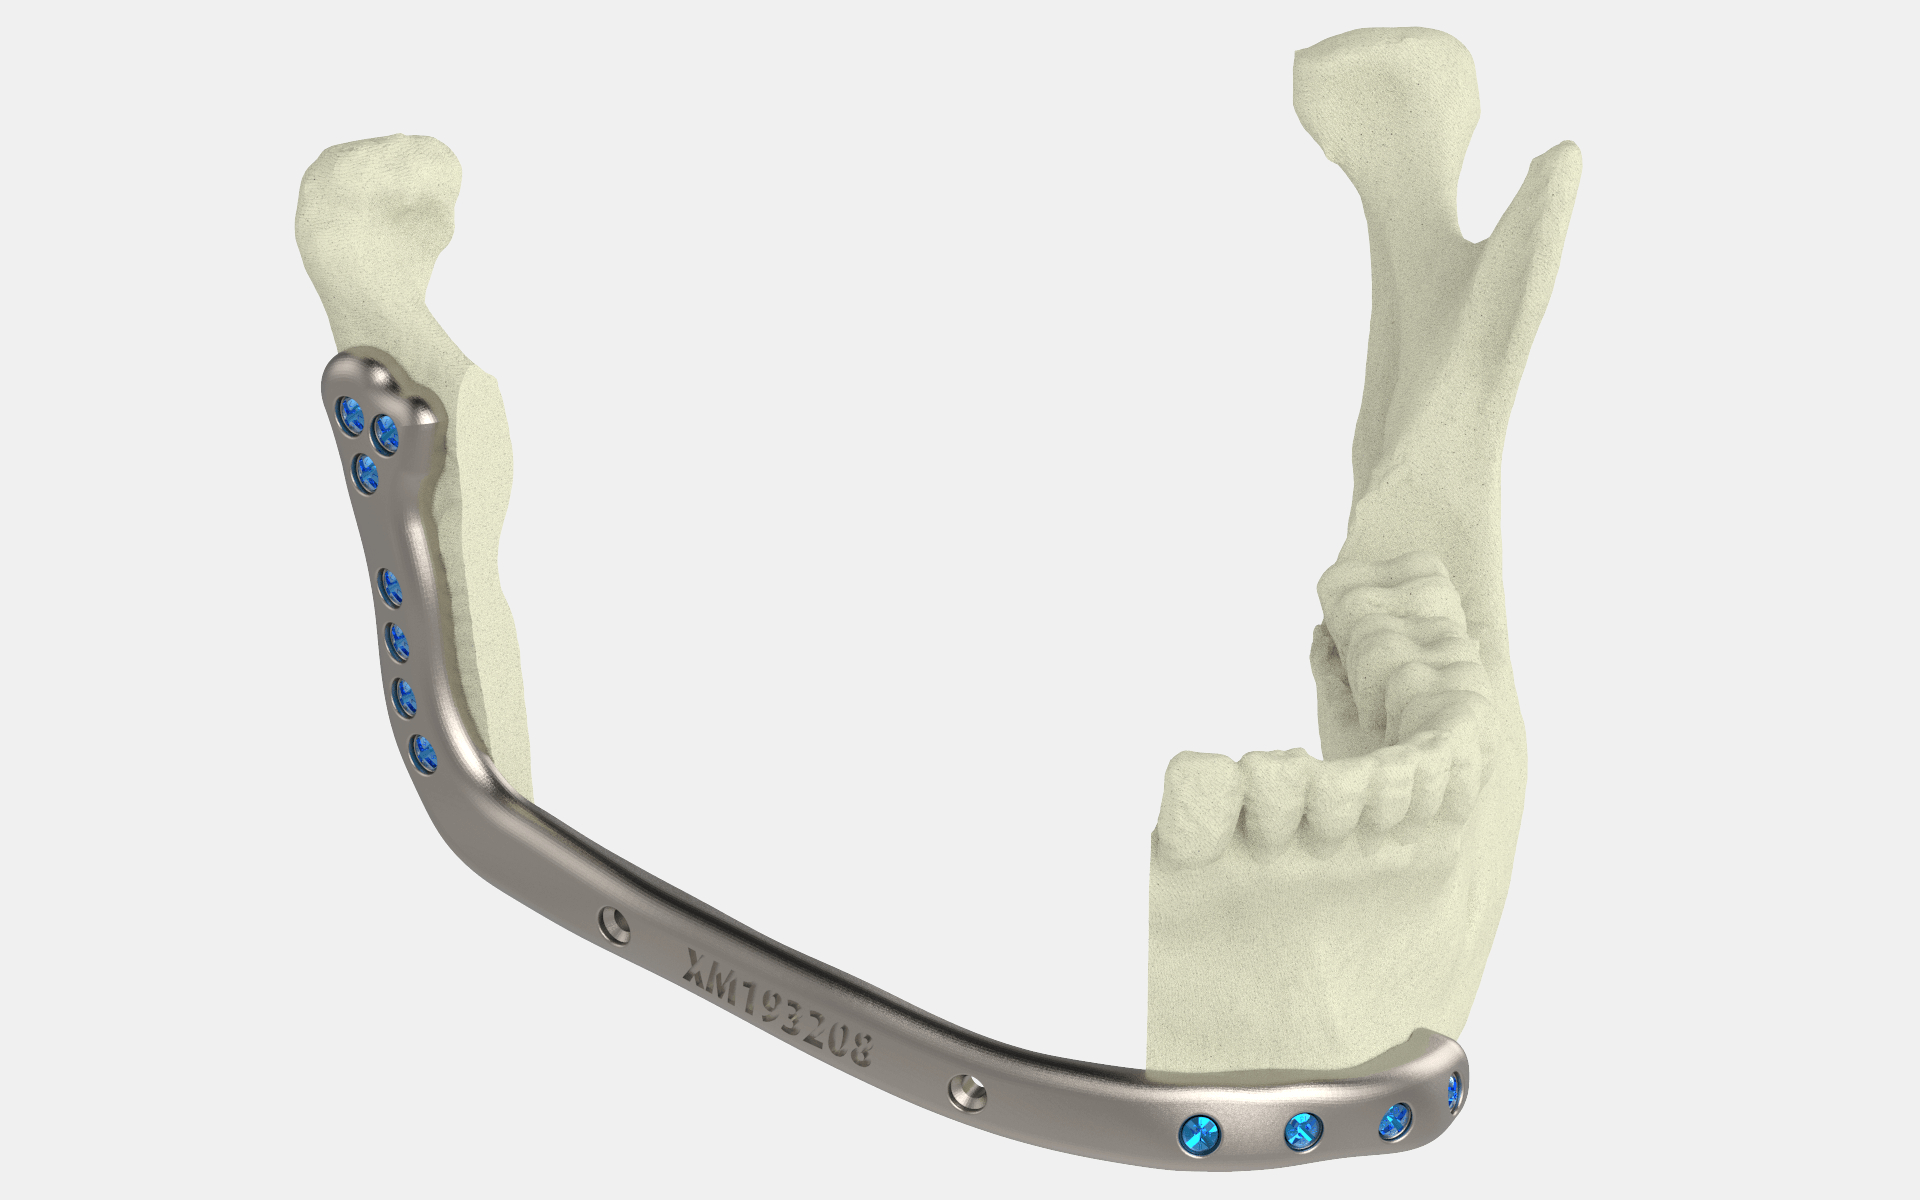

△3D打印医疗植入物

加拿大卫生部已经批准了第一款本土制造的3D打印医疗植入物。据了解,这是一款可定制的下颌骨(下颚)板3D打印植入物,主要用于口腔癌患者的面部重建手术。此外,它还可以与手术指南一起使用,用于切割和钻孔操作。该植入物被命名为Specifit 3D下颌骨板,由魁北克市的3D解剖构造实验室(LARA 3D)开发。LARA 3D是魁北克投资局(CRIQ)的分部,该机构为新企业提供产品开发服务。植入物的创建也得到了大学医院CHU de Québec-Université Laval、骨科螺钉制造商AlkomDigital和金属粉末公司AP&C(GEAdditive公司)的支持。

为了能够进行下颌骨重建手术,下颌骨板是必要的,该装置用于对齐和稳定重建手术中的几块骨头,同时促进愈合和长期骨融合。Bernier补充说:"它不仅将改善患者的生活质量,而且由于优化、引导和个性化的手术,它还将使魁北克大学-拉瓦尔大学研究中心的3D医疗设备专业中心得到发展。我们相信,这项技术的批准只是标志着LARA 3D公司在3D医疗打印方面的创新、研究和发展的开始。“

Specifit 3D下颌骨板

加拿大卫生部于2021年9月批准了Specifit 3D下颌骨板的使用,使外科医生能够使用该植入物以及两个手术切割和钻孔指南来治疗病人。根据这项批准,3D Specifit下颌骨板必须使用生物相容性材料进行3D打印。医学专家使用23级钛来生产这款植入物,利用激光粉末床熔化(用于制备植入物)或电子束熔化(用于两个手术切割和钻孔指南)。由于该设备的设计是可定制的,因此病人特定的治疗需求将大大受益。植入物可以根据病人的解剖结构进行3D打印,这将有助于提高手术成功率,并减少手术和恢复时间。 CRIQ副总裁Lyne Dubois补充说:" LARA